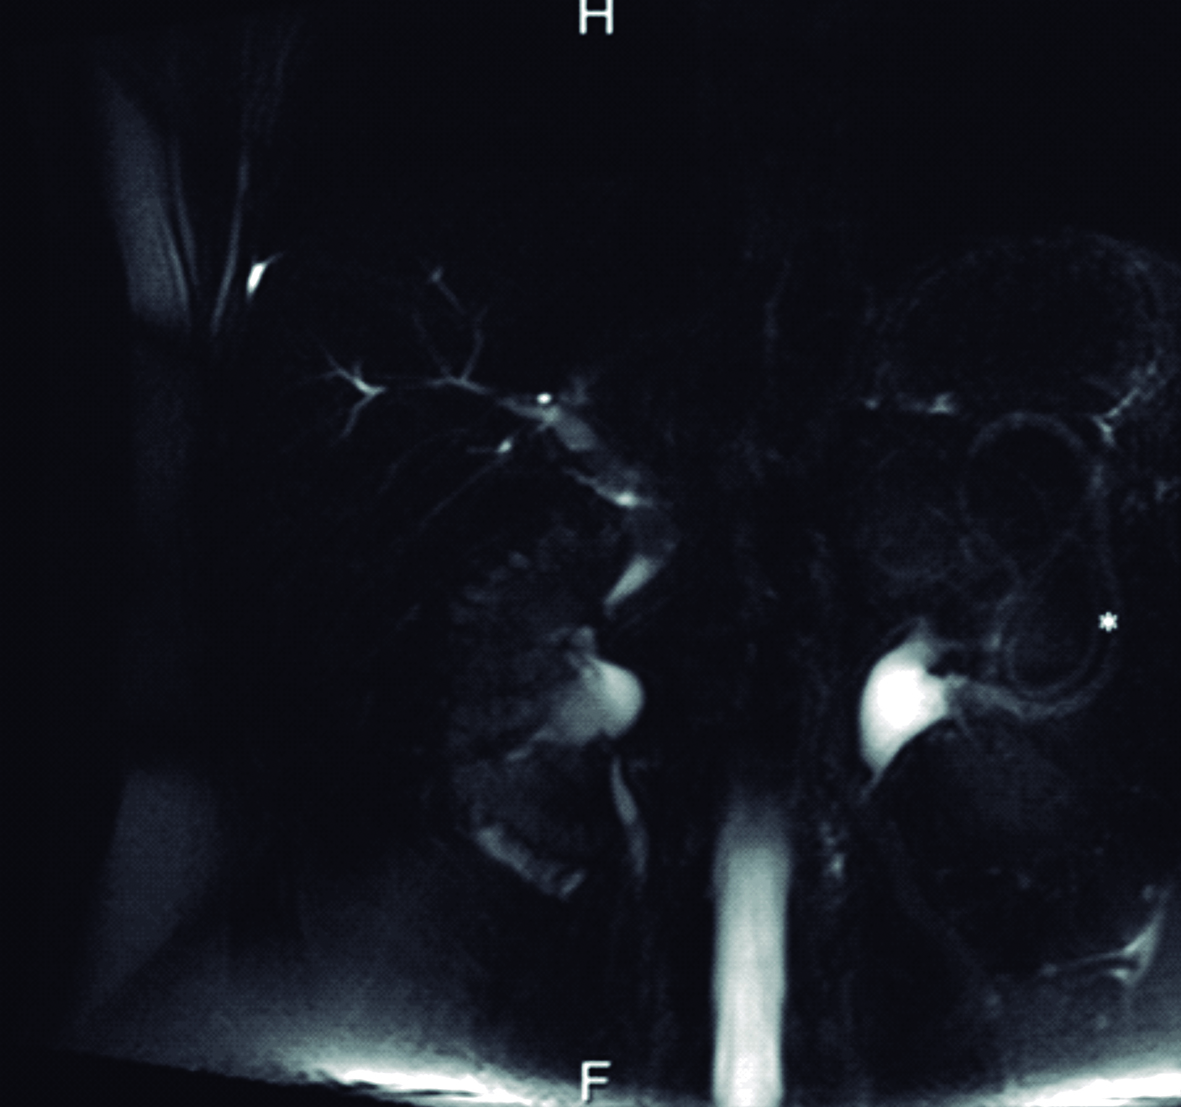

Figura 5. Colangiografía por Resonancia Magnética - Reconstrucción

Se visualiza vía biliar intra y extrahepática de calibre habitual, sin defectos de relleno.